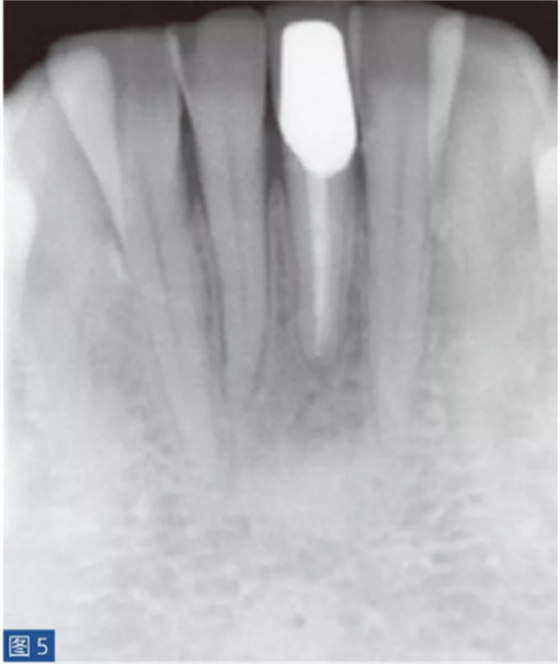

牙齒無癥狀的根尖周炎(圖4 和5)是由牙髓壞死引起的,并且通常是在癥狀性根尖周炎之后發(fā)生。因此,對(duì)冷、熱刺激和牙髓電活力測(cè)試無反應(yīng)。叩診無或者引起輕微的疼痛。如果骨皮質(zhì)已經(jīng)發(fā)生改變并且涉及到口腔軟組織,則觸診可引起輕微不適。放射學(xué)檢查,可能出現(xiàn)硬骨板不連續(xù)(破壞)以及根尖周和牙間組織的廣泛性破壞。

圖4:31 牙齒AAP。術(shù)前X線片?;颊咴V叩診和觸診時(shí)有輕微疼痛。

圖5:31 牙齒AAP。根管再治療12 個(gè)月后。